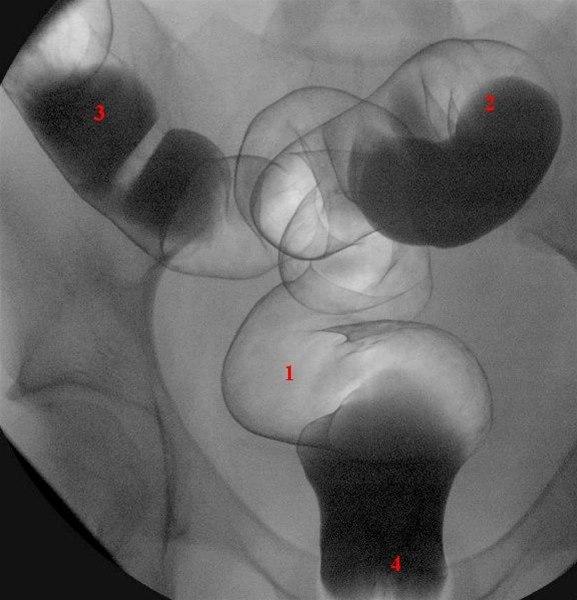

Rektum (1) og sigmoideum (2 og 3) i frontalprojeksjon

Ballongkateter i rektum (4) er delvis skjult av barium